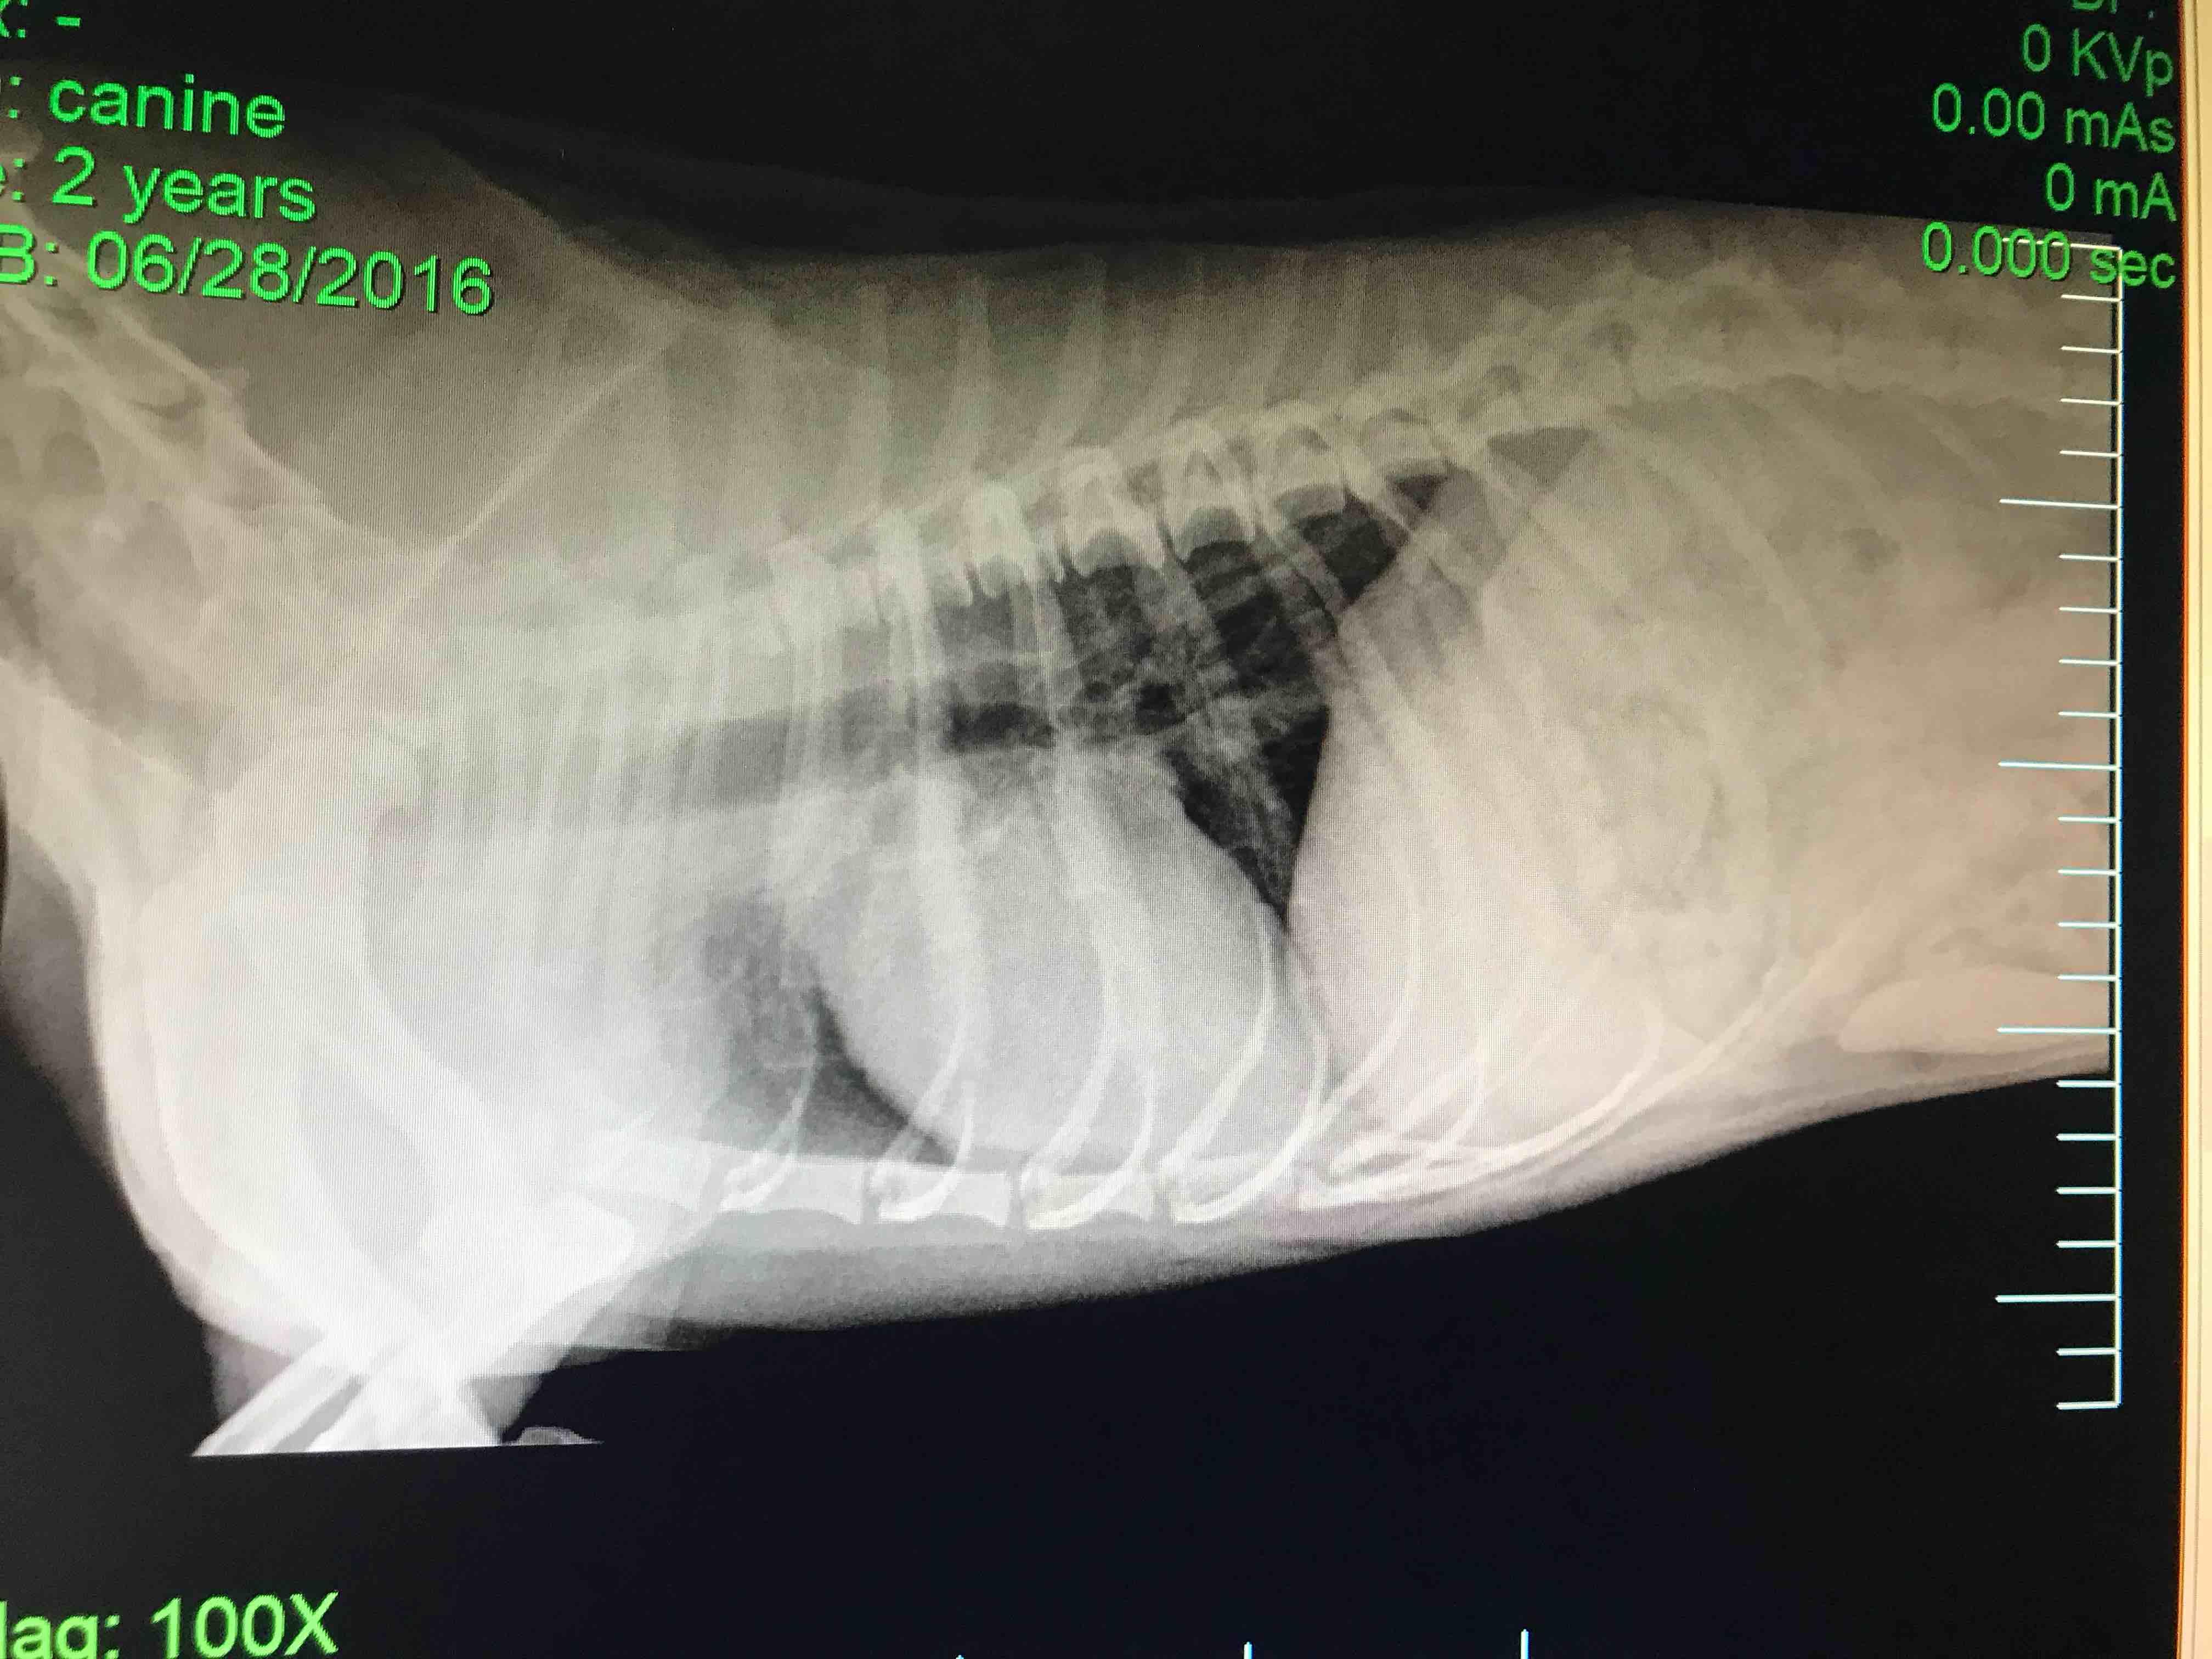

Pet's info: Dog | Mixed Breed | Male | neutered | 2 years and 3 months old | 20.08 lbs

Last question I posted, someone said I needed a VD of the heart. Here it is. I had one doc said his heart look bad and he recommended a ultrasound. second opinion said he looks normal and a third said his head looked ehhhhh. I don’t know who to believe. So here I am. How does his heart look? Does it look normal? Reason for this, He’s been getting tired more easily and takes more breaks.

I don’t think the heart looks terribly enlarged, maybe on the big side of normal. Ask the vet who took the rads if they are able to submit them to a radiologist for review. (A radiologist is a vet who spent at least 3 additional years to do a residency to specialize and study only imaging. Their expertise is really valuable in cases that are not clear cut and obvious.) If his lab work is all normal, and a radiologist is concerned about the appearance of the heart, then it’s logical to seek out an echocardiogram (ultrasound of the heart) by a veterinary cardiologist. If a radiologist does NOT think the heart looks questionable, and Boo’s lab work is all normal, it might be worth considering an abdominal ultrasound (sonogram of the belly) to see if there are any abnormalities there (enlarged lymph nodes, abnormal spleen, any abnormality in GI or urinary tract, etc). I hope that’s helpful, sorry there is no easy clear cut answer. Interpreting X-rays is like looking at 1 piece of a puzzle. History and clinical signs, physical exam, lab work, and other imaging all tie in to the bigger picture. If you would like to have a consult, I may be able to help you further with more information, and would do my best to help point you in the right direction. Thanks for asking Petco Pet Education Center, formerly Petcoach!